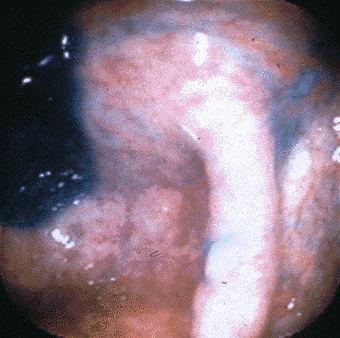

화상상에서 악성 림프종과의 식별이 필요했던 O157대장질환의 일례 (후쿠오카시 미나미구、타카미야외과)

염증성 및 궤양성질환/병원성대장염

대장/기타

내시경